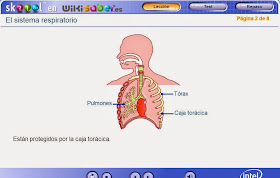

9. PULMONES

Son 2 órganos situados en el interior de la caja torácica (costillas,

esternón y parte de columna vertebral), la cual está cerrada inferiormente por

el diafragma (músculo que interviene en la respiración). El

pulmón derecho es mayor que el izquierdo, ya que este segundo deja un espacio

al corazón. En consecuencia, el pulmón derecho posee 3 partes

o lóbulos y el izquierdo tan sólo 2. Rodeando cada pulmón

aparecen 2 membranas llamadas pleuras, entre las cuales hay un

líquido viscoso.

El bronquio que penetra en cada pulmón se va ramificando y da numerosos tubos estrechos llamados bronquiolos, estos finalizan en ensanchamientos llamados sacos alveolares. Cada saco alveolar contiene numerosos alvéolos, en ellos es donde se realizará el intercambio gaseoso. Rodeando a los sacos alveolares aparecen multitud de pequeños vasos sanguíneos llamados capilares.

Considerando los dos pulmones hay unos 500 millones de alvéolos pulmonares.

OTRAS ESTRUCTURAS RELACIONADAS

- Arteria pulmonar. Contiene sangre pobre en oxígeno y rica en dióxido de carbono, que se mueve desde el corazón hacia los pulmones.

- Vena pulmonar. Contiene sangre rica en oxígeno y pobre en dióxido de carbono que se mueve desde los pulmones hacia el corazón.

- Músculos intercostales externos. Son los que levantan las costillas para aumentar el volumen de la cavidad torácica y así producir la inspiración.

- Costillas

- Pleuras. Son dos membranas que rodean los pulmones. El espacio que hay entre ellas está lleno del denominado líquido pleural. Su finalidad es evitar el roce entre los pulmones y las costillas.

- Cavidad torácica. Es la cavidad formada por las costillas y el esternón, dónde se alojan los pulmones.

- Cavidad cardíaca. Es una concavidad en el pulmón izquierdo en la que se aloja el corazón.

- Diafragma. Músculo plano que durante la inspiración desciende permitiendo la dilatación pulmonar y durante la espiración asciende favoreciendo el vaciado de los pulmones.